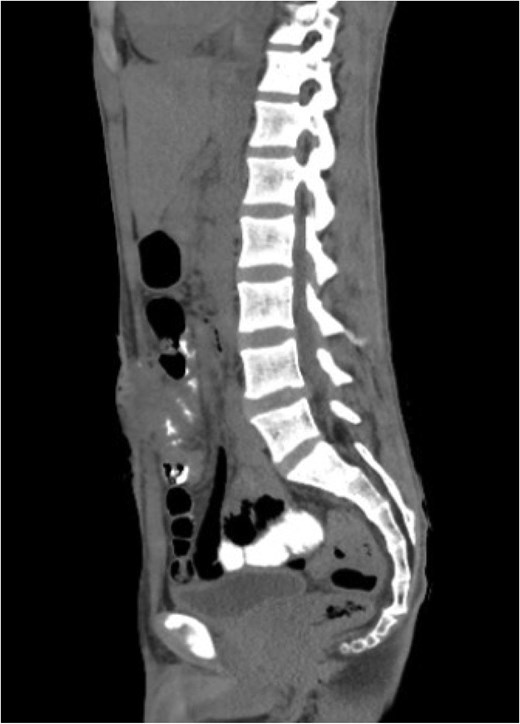

Sagittal view of abdominal and pelvic CT scan with IV and oral contrast shows anterior abdominal wall collection near the supra-umbilical wound with faint linear contrast within the collection representing enterocutaneous fistula.